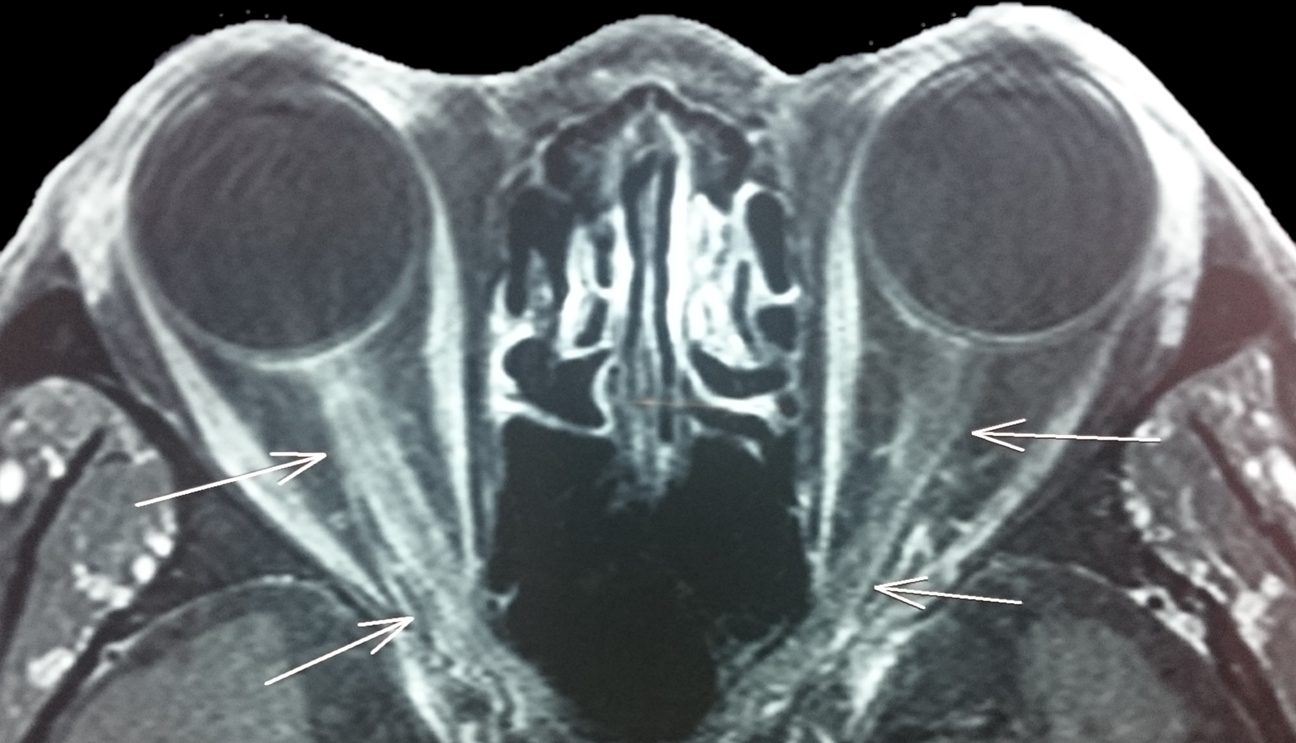

視神經炎患者的磁力共震影像

視神經發炎是其中一種最常見的視神經疾病,這種眼疾較常見於年輕人,典型的視神經炎常見於20-40歲人士,而非典型的則常見於40-60歲病人。病徵包括視野出現間竭性視野模糊,亦有病人會出現眼部周圍不適以及看顏色比較暗淡的情況,更有部分病人會出現視神經乳頭腫脹。醫生通常會使用亮光交替照射雙眼,觀察瞳孔反應以協助判斷病人是否患上視神經炎;另外亦會留意病人有否出現色差或視力轉差的情況。但要真正確診就需要利用顯影對照的磁力共震掃描對視神經作檢查。

(照片由作者提供)